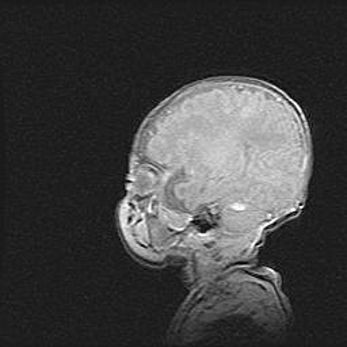

Церебральная ишемия II.

Возраст: 5 дней

Вес: 3400 г

Пол: женский

Окружность головы: 35 см

Срок гестации: 39 недель

Церебральная ишемия – это заболевание, характеризующееся недостаточностью (гипоксией) либо полным прекращением (аноксией) снабжения мозга кислородом по причине закупорки одного или нескольких сосудов. Это приводит к  что метаболическим расстройствам различной степени тяжести в тканях головного мозга, развитию коагуляционных некрозов и гибели нейронов.